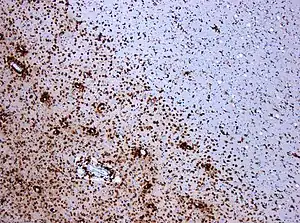

A combination of histologic and/or immunohistochemical stains can be used to visualize post-mortem MS characteristic lesions and to diagnose post-mortem "inflammatory demyelinating lesions consistent with MS":[12]

- hematoxylin and eosin stain (demonstrates tissue and cell morphology)

- myelin stains (Luxol fast blue/periodic acid-Schiff, Luxol fast blue/hematoxylin/eosin, or immunohistochemistry for myelin proteins)

- macrophage-specific markers (immunohistochemistry for KiM1P or CD68)

- stains for axons (Bielschowsky silver impregnation or immunohistochemistry for neurofilament protein)

- stains for astrocytes (hematoxylin and eosin or immunohistochemistry for glial fibrillary acidic protein) and

- stains for the different lymphocyte subtypes (immunohistochemistry for CD3, CD4, CD8, CD20, and/or CD138)

These markers are specific for the different processes that drive the formation of plaques: inflammation, myelin breakdown, astrogliosis, oligodendrocyte injury, neurodegeneration, axonal loss and remyelination. MS lesions evolve differently during early versus chronic disease phases, and within each phase, different kind of activity appears.

The classification system for the lesions was updated in 2017. This system classifies MS lesions as active, mixed active/inactive, or inactive lesions based on the presence and distribution of macrophages/microglia. They locate the slowly expanding lesions inside the mixed subtype and provide a description of the different lesion types and required staining techniques.[13]

Pre-active lesions are lesions in an early stage of development. They resolve sometimes without further damage, and not always develop into demyelinating lesions. They present clusters of activated microglia in otherwise normal-appearing white matter.[100][101]

NAWM is the place where lesions appear and the process seems to be made by microglia, in absence of leukocyte infiltration, astrogliosis or demyelination. At the final stage of the process, these microglia develop into active demyelinating MS lesion[153]

Microglial nodules

Originally proposed as a biomarker,[165] the presence of these nodules has a possible pathogenetic significance. Though their role in the lesion evolution is still unclear, their presence in normal-appearing white matter have been suggested to be an early stage of lesion formation [166]